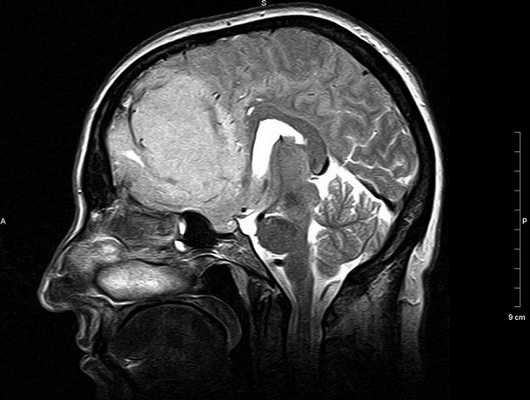

МР-сканирование при подозрении на менингиому мостомозжечкового угла, сагиттальная проекция

Метод основан на использовании магнитного поля, под действием которого атомы водорода в молекулах воды начинают резонировать. Колебания заряженных частиц фиксируют специальные датчики, информацию обрабатывают с помощью компьютерной программы и преобразуют в серию послойных фотографий рассматриваемой области.

В диагностике патологических изменений ЦНС в области ствола используют МРТ головного мозга с прицельным осмотром мосто-мозжечкового угла (ММУ). Сканирование необходимо для уточнения состояния данного участка и выявления патологических изменений нервных корешков.